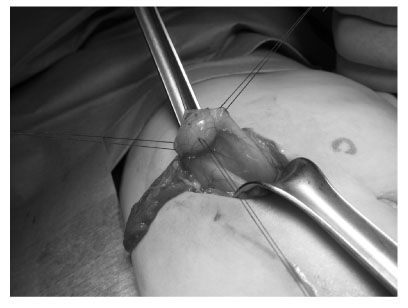

Fig. 3

Operative finding of gastric duplication which was located at the greater curvature, distal part of the stomach, measuring about 1 cm in diameter.

Fig. 3 Operative finding of gastric duplication which was located at the greater curvature, distal part of the stomach, measuring about 1 cm in diameter.